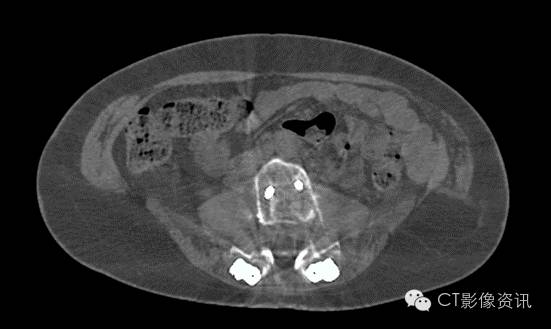

前列腺粒子植入术后

Without MAR

With MAR

Smart MAR 有效地消除掉由于光子饥饿效应带来的白色放射状伪影.